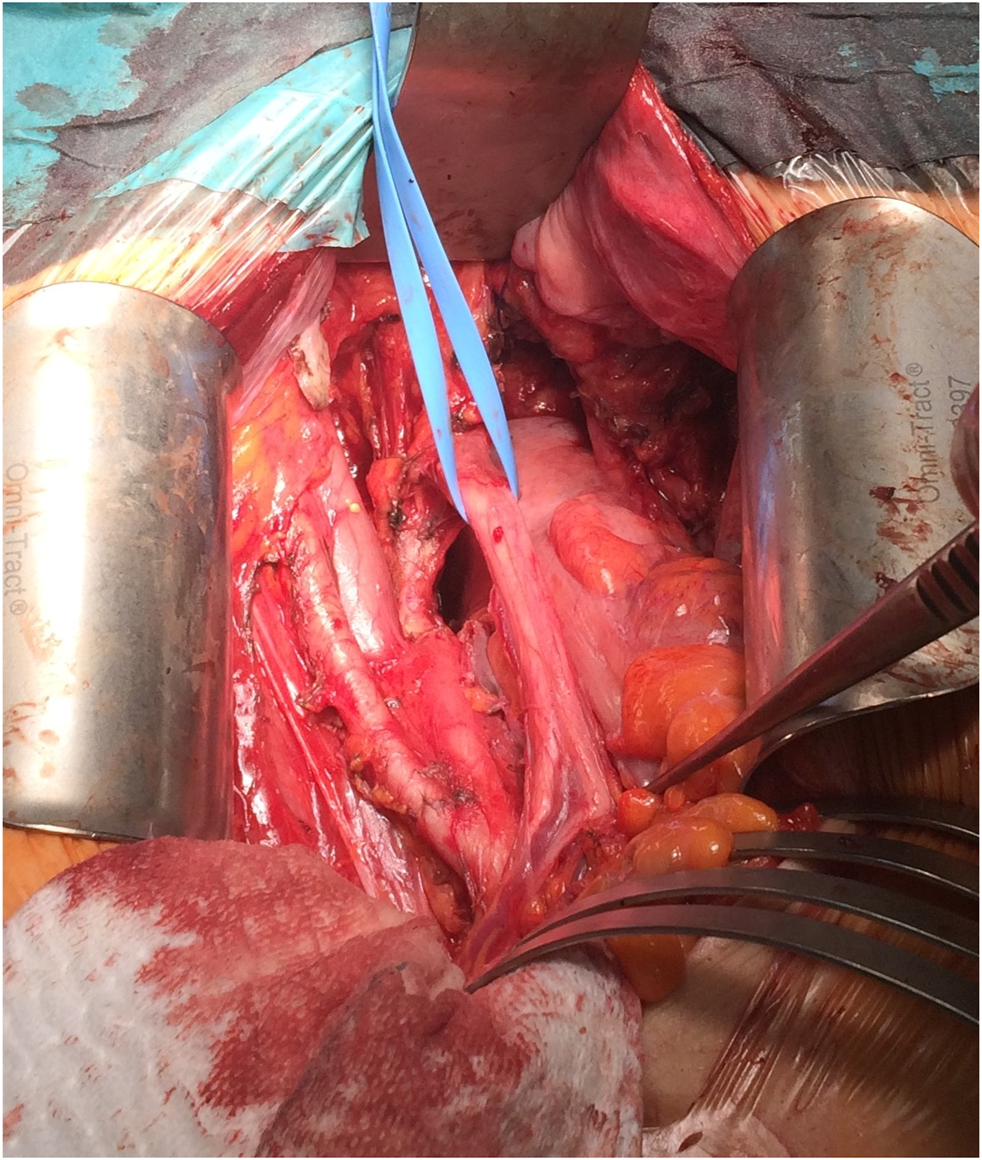

Radical hysterectomy involved removing the cervix, uterus, Fallopian tubes, and ovaries, together with the parametria and upper vagina, followed by parailiacal and pelvic/obturator lymphadenectomy in the pelvic retroperitoneal space (Figure 3).

FIGURE 3

Intraoperative picture, with the preparation of parailiacal and obturator space.